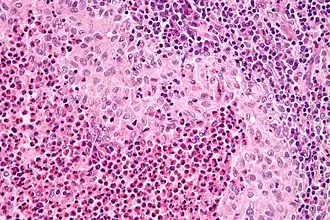

Langerhanscelhistiocytose (LCH), ook wel bekend onder oudere namen Histiocytosis X, ziekte van Hand-Schüller-Christian of de ziekte van (Abt-)Letterer-Siwe, is een ziekte waarbij er sprake is van een woekering van langerhanscellen in de lichaamsweefsels. Deze cellen spelen een rol bij de afweer en het immuunsysteem. De ziekte behoort tot de grotere groep van de histiocytosen.

De diagnose wordt gesteld door histologisch onderzoek van een weefselbiopt.